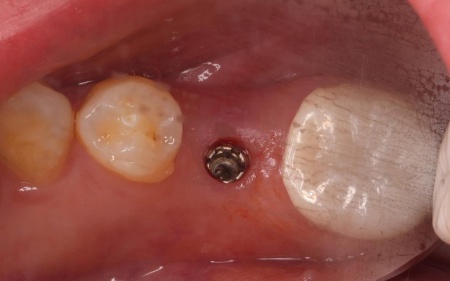

治療後